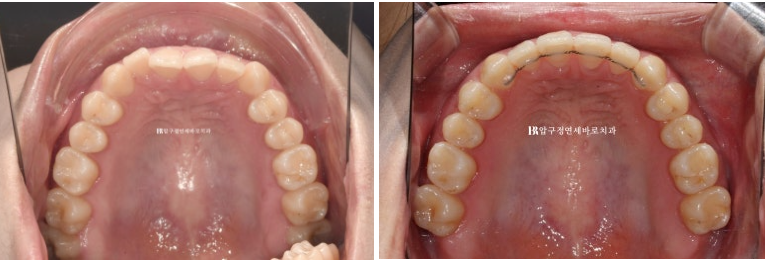

24.02~24.11

뒤로 쓰러져 있던 앞니가 나오면서 악궁모양이 네모진 형태에서 원형으로 바뀌었습니다.

아래 악궁모양이 좋아졌습니다.